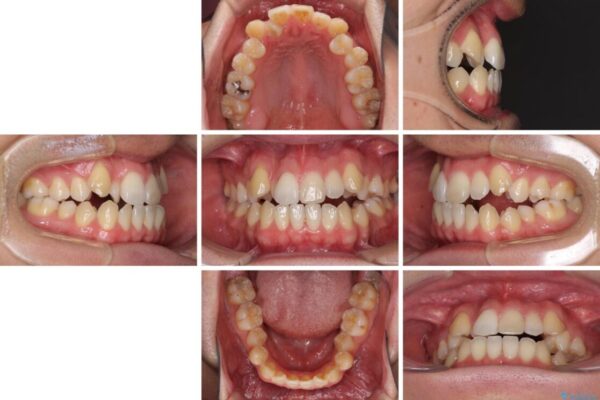

左右の八重歯が気になる ワイヤー装置での咬み合わせ改善

八重歯と前歯のデコボコを気にして来院された患者様です。

治療計画

営業職であり、商談などで飲食をする機会が多いとのことで、インビザラインではなく、ワイヤー装置にて矯正治療を行うこととしました。

治療後について

舌の突出癖がなかなか改善されず、上下前歯部の接触が得られるまでに予定の倍ほどの期間がかかりました。

治療前

治療途中

治療後